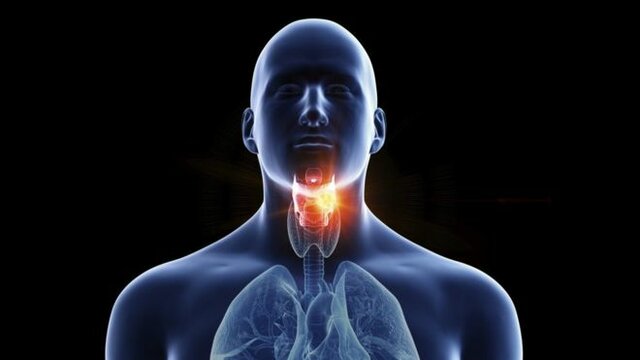

آسان ترین و سریع ترین راه تسکین گلو درد

گلو درد میتواند دردناک و آزاردهنده باشد و با برخی روش ها به راحتی می توان گلو درد را درمان کرد.

به گزارش اکسپرس، اگر گلو درد دارید، ممکن است بوی بد دهان، سرفه خفیف و تورم غدد گردن داشته باشید. گلو درد یکی از سه نشانه اصلی ویروس کرونا نیست (درجه حرارت بالا، سرفه جدید و مداوم، یا از دست دادن یا تغییر حس بویایی یا چشایی).

با این حال، گلو درد میتواند یکی از علائم اولیه ویروس کرونا باشد. بیشتر اوقات، گلودرد ناشی از ویروسهای مسری مانند سرماخوردگی یا آنفولانزا است، اما همچنین میتواند ناشی از سیگار کشیدن باشد.